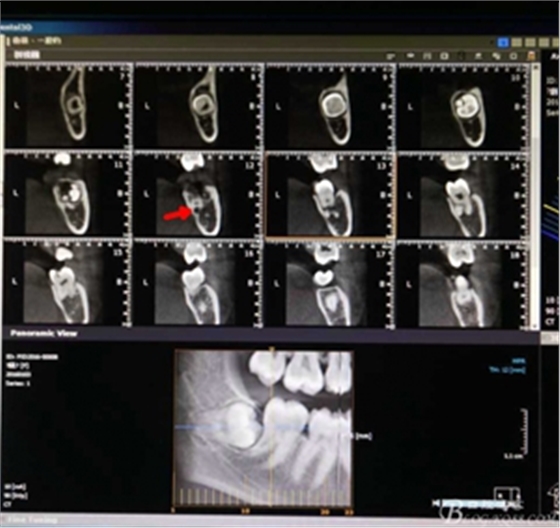

圖3.冠向檢查:38牙根未進(jìn)入下頜管內(nèi),牙冠周圍有牙囊影。

圖4.術(shù)前的CBCT縱剖面檢查:38牙根1/3緊鄰下頜管,看紅色箭頭。提示盡量不要斷根,如根尖折斷,取根導(dǎo)致下頜神經(jīng)損傷的風(fēng)險(xiǎn)加大